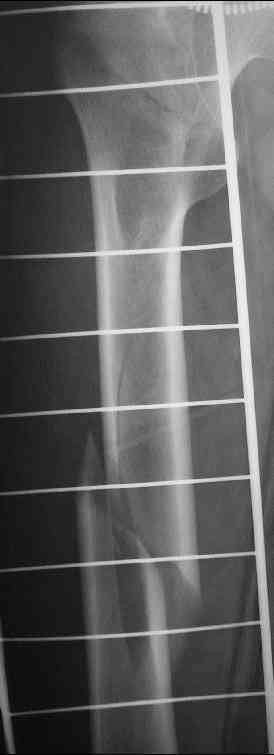

Уважаемые коллеги,пару дней назад к нам поступил пациент 54 лет с таким вот переломом правого бедра. Сейчас на скелетном вытяжении. Хотелось бы услышать мнения по поводу природы округлого просветления в подвербельной области (аневризмальная киста?)и тактики лечения.

Dear all, a few days ago a 54 y.o. patient was admitted to our hospital with this fracture of the right femur. Now he is on a skeletal traction. I'd appreciate your opinion as to: 1.the nature of a lucent lesion (?) in subtrochanteric area - is it ABC? 2.treatment options.Thanks, Peter Romchuk, Central City Hospital, Rivne, Ukraine.С уважением, Петр Ромчук, ЦГБ г.Ривне, Украина